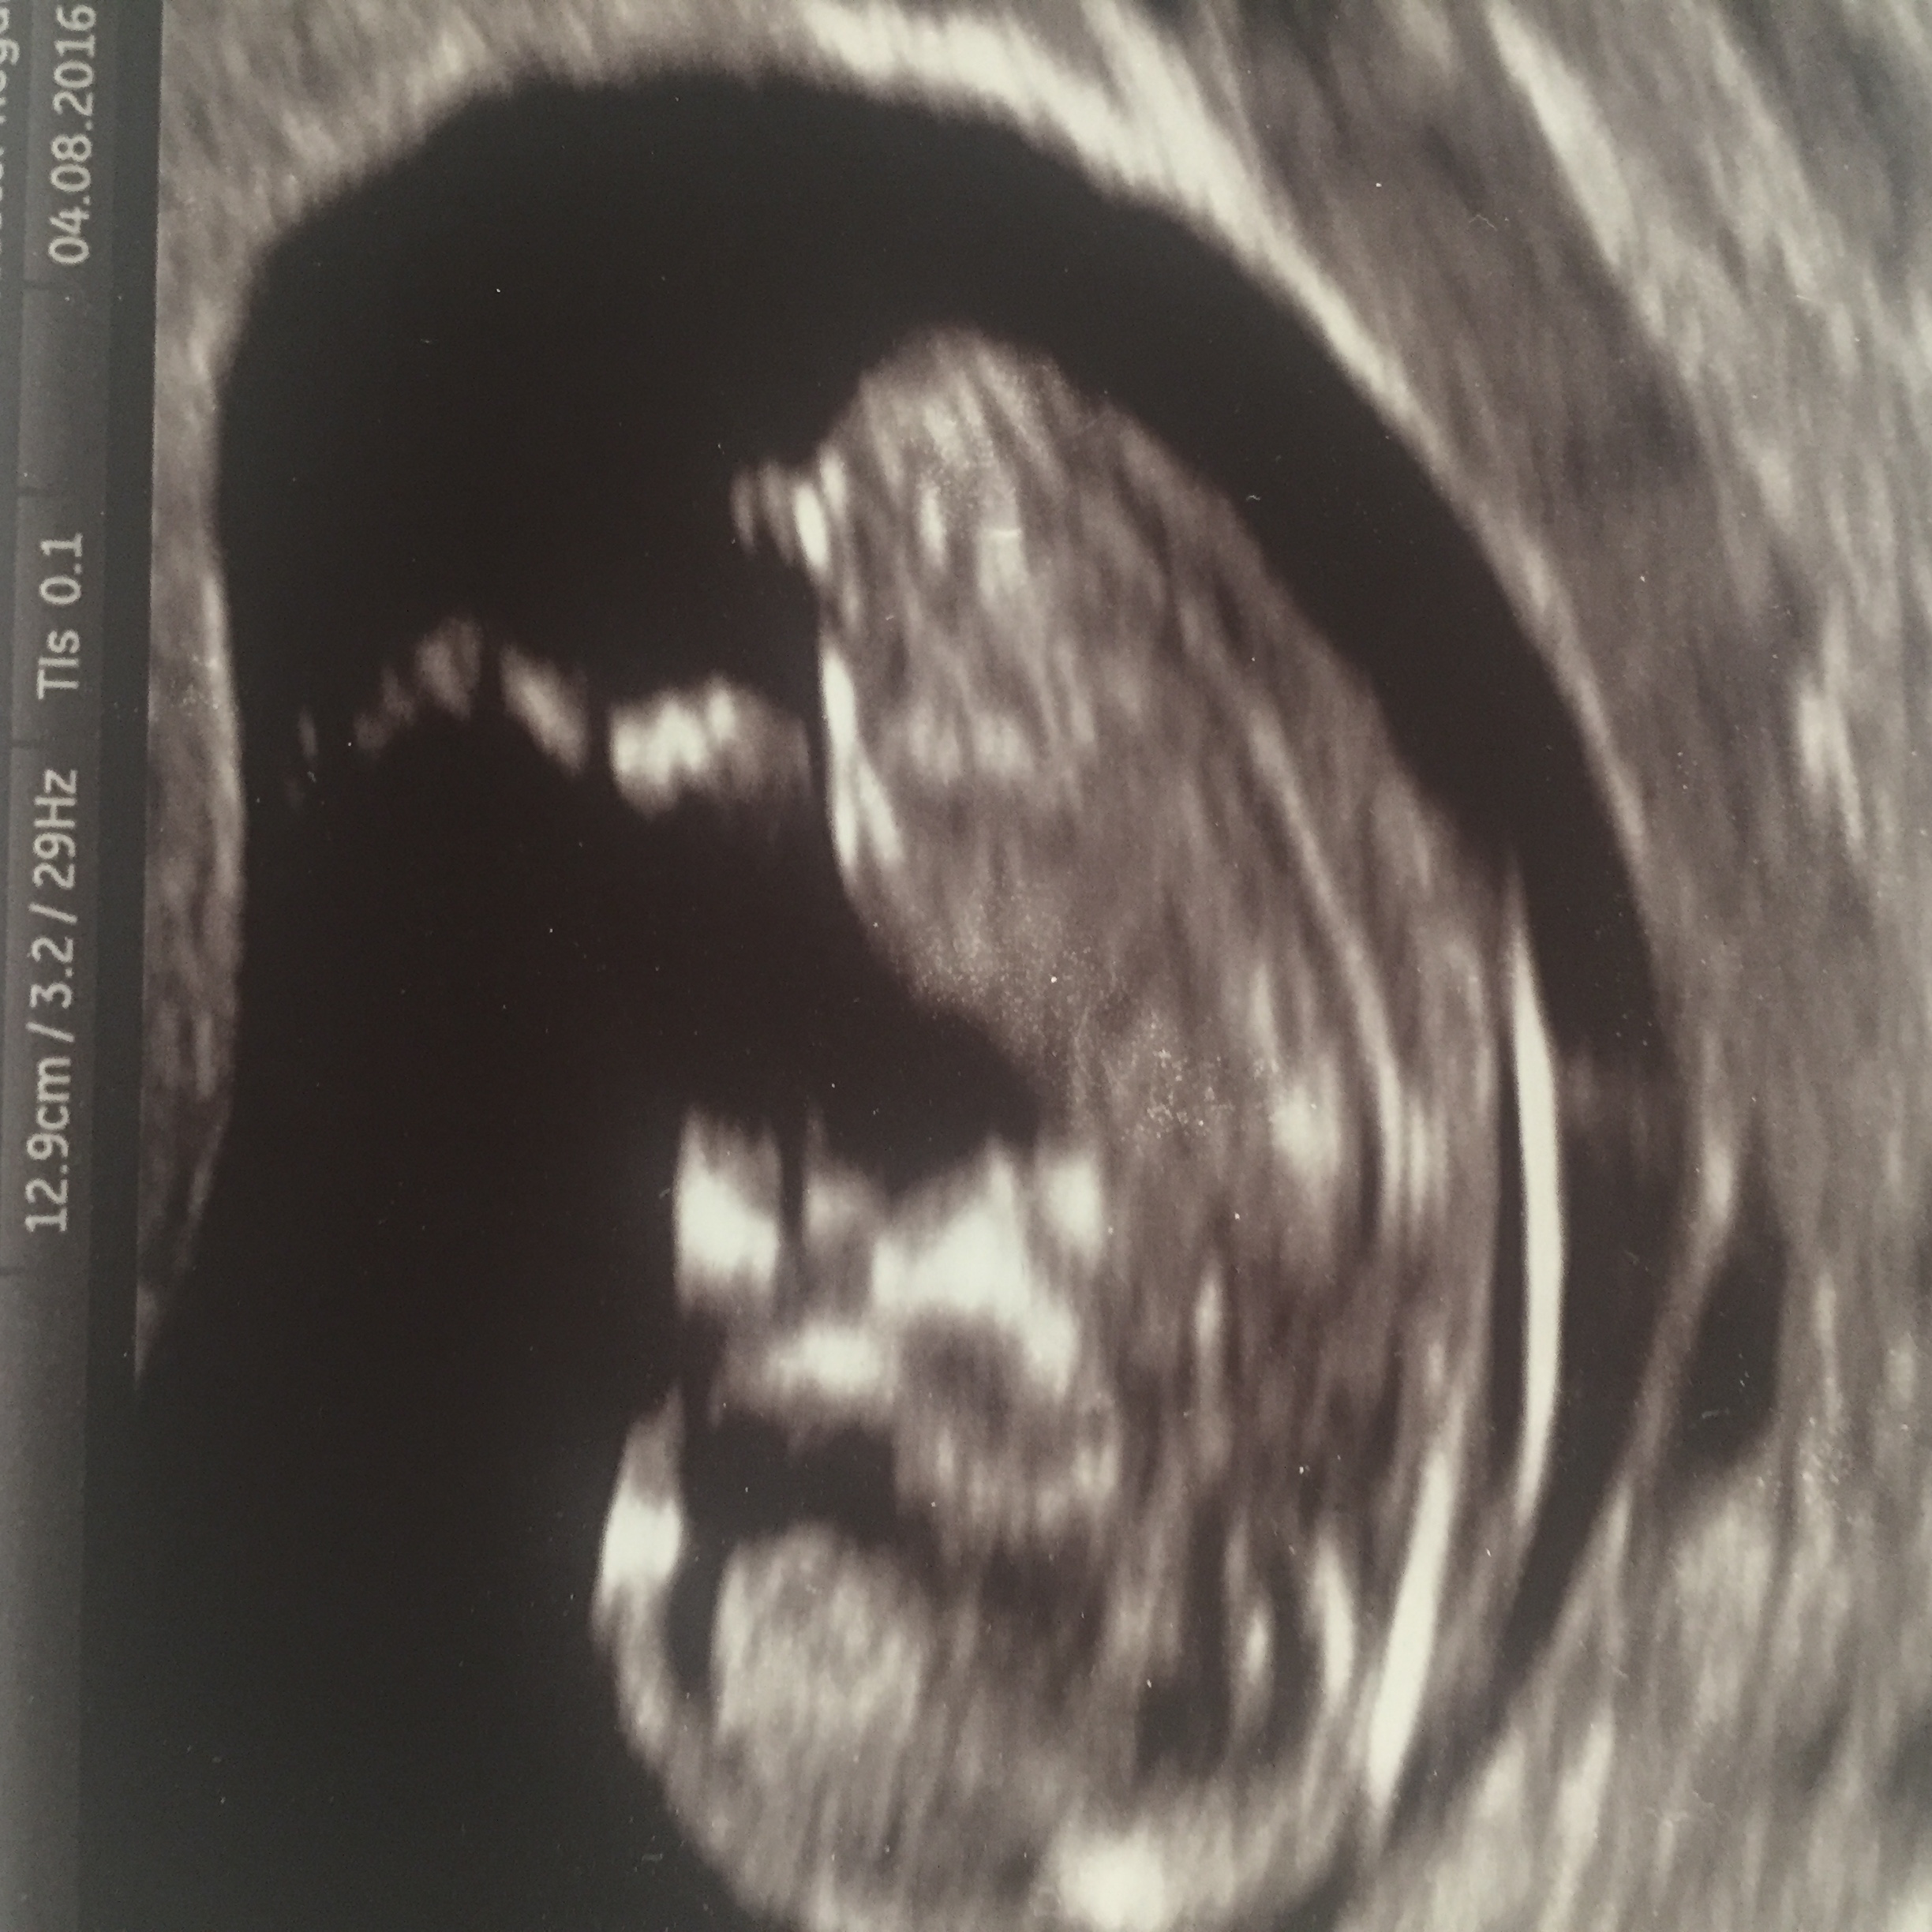

I'm new at this gender guessing but il say boy!

Classic boy!x

100% a boy!

What makes u think boy? I didn't know if that bright white sticking up part is actually the babies cord or leg?

The leg seems to be the longer section floating nearer the body/tummy. I'd say that's all nub, very like my 2nd boy's....

That thing that is sticking up is a boy nub. Do you have more pics?